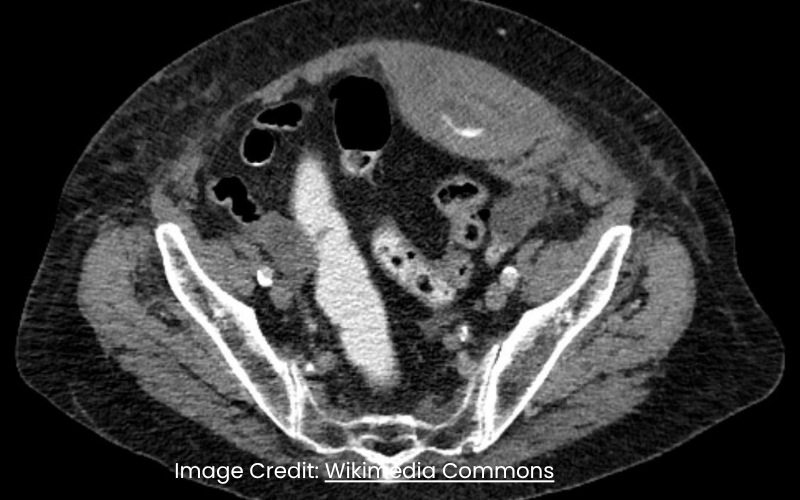

Abdominal Emergencies | Oct 31, 2025

Rectus Sheath Hematoma in Adults: Diagnosis and Conservative Care

Samatha Ampeti, et al.

Rectus sheath hematoma (RSH) is an uncommon cause of acute abdominal pain, accounting for less than 2% of cases. It arises from rupture of the...Read More